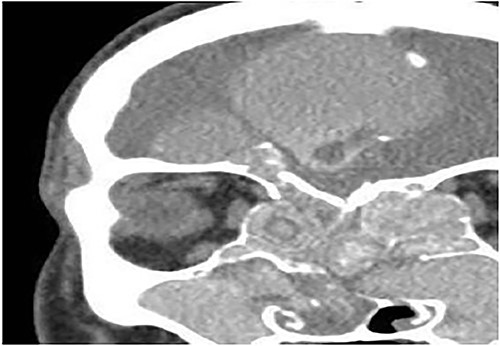

A 8-year-old female with known bronchial asthma presented with right nasal obstruction & mild right eye proptosis for 9 months. Endoscopic nasal examination showed multiple right nasal polyps. CT scan of the paranasal sinuses (Fig. 4) and FESS confirmed the diagnosis of right-sided allergic fungal pansinusitis. After 3 years, she presented with left-sided nasal obstruction & discharge. Upon performing the endoscopic nasal examination, multiple nasal polyps were found in the left nose. CT scan of the paranasal sinuses (Fig. 5) confirmed the diagnosis of left-sided allergic fungal pansinusitis, but the operated right-sided sinuses were normal. The child remained symptoms-free for 5 years follow-up.

Coronal CT paranasal sinuses shows heterogeneous opacities filling the right frontal sinus with extension through the right frontal recess. It involves the ethmoid sinus with expansion. The right lamina papyracea shows lateral displacement with partial dehiscence and nasal polyposis.